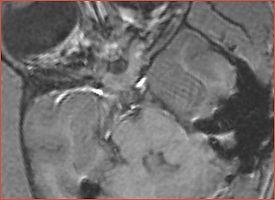

Valentino has structure not consistent with the normal anatomy Ron: this is likely a cyst.